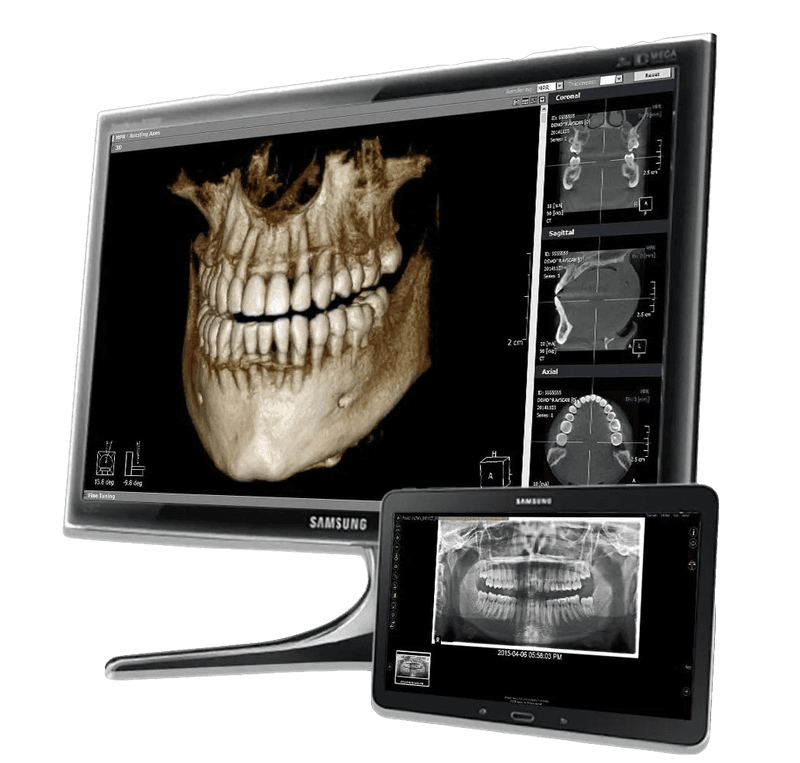

Итальянское оборудование OMS

Ультраточные снимки:

КТ и ОПТГ

КТ и ОПТГ

Новейший 3D-сканер для полного обследования

Самые современные подходы к лечению